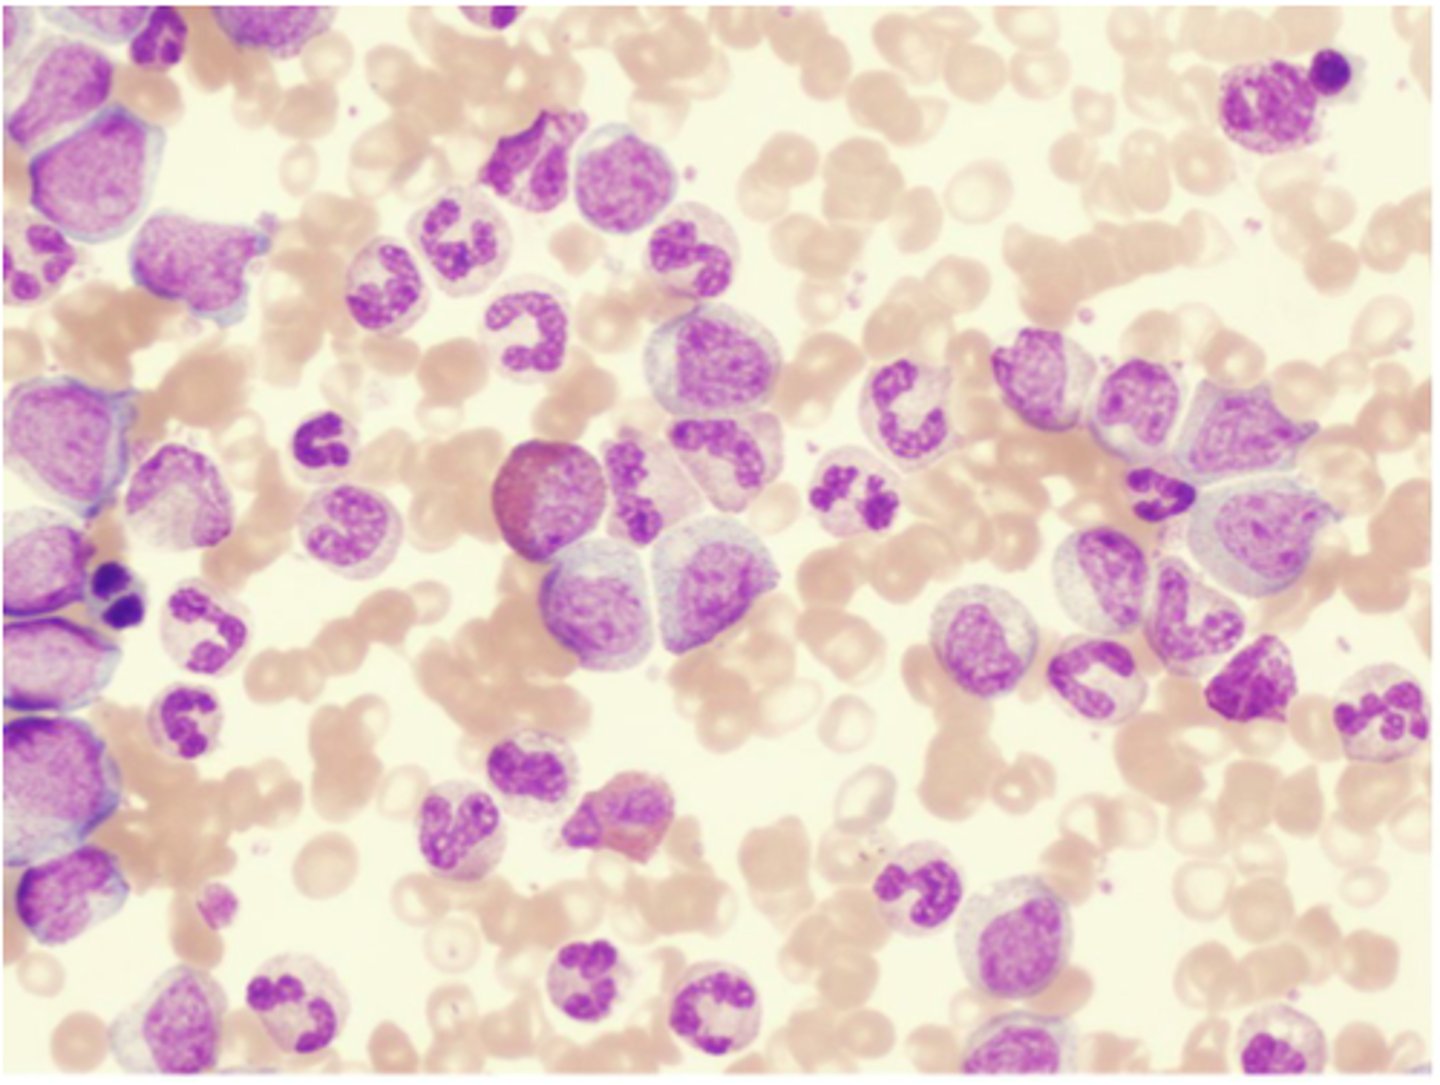

Acute Leukemias

Large numbers of immature BLAST leukocytes in the blood and bone marrow (rapid onset and progression)

Acute lymphocytic leukemia (ALL)

Acute leukemia of lymphoid stem cells that occurs in children and adolescents

Acute myelocytic leukemia (AML)

Acute leukemia of myeloid stem cells that occurs in older adults